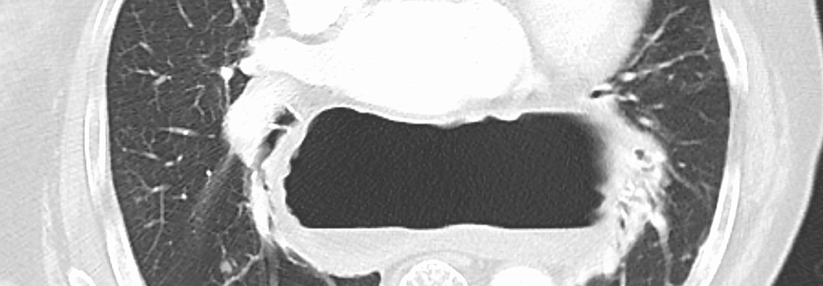

Kettenreaktion mit schwerwiegenden Folgen: Auf die gastroösophageale Refluxkrankheit folgt der Barrett-Ösophagus. Daraus entsteht dann nicht selten der Krebs. Kettenreaktion mit schwerwiegenden Folgen: Auf die gastroösophageale Refluxkrankheit folgt der Barrett-Ösophagus. Daraus entsteht dann nicht selten der Krebs. © Judith – stock.adobe.com

Das Barrett-Karzinom droht zur Volkskrankheit zu werden. Vor allem Männer sind gefährdet. Ein Score kann dabei helfen, diejenigen mit Barrett-Ösophagus herauszufiltern, für die die Krebsgefahr am größten ist. Dann heißt es: präventiv behandeln!

Trotz 30 Jahren PPI: Die gastroösophageale Refluxkrankheit wird immer häufiger und auch die Prävalenzen von Barrett-Ösophagus und -Karzinom nehmen zu. Zudem ist die Prognose des Barrett-Karzinoms unverändert schlecht. Die Fünf-Jahres-Überlebensrate beträgt nur 25 %. Folgt man Daten aus den Niederlanden und Großbritannien, so wird im Jahr 2030 einer von 100 Männern ein Barrett-Karzinom entwickeln, berichtete Professor Dr. Joachim Labenz vom Diakonie-Klinikum Jung-Stilling in Siegen. Bei Frauen sei dies etwa 20 Jahre später zu erwarten. „Das heißt, wir müssen uns Gedanken um dieses Thema machen. So, wie wir es bisher gemanagt haben, funk­tioniert es jedenfalls nicht.“